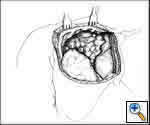

Any anterior mediastinal mass (Figures 1, 2) must be considered suspect for germ cell tumor, especially in a young male. Errors in diagnosis are not uncommon and can result in mismanagement of a potentially curable patient. All patients with an anterior mediastinal mass should have alpha-fetoprotein (AFP), β-human chorionic gonadotropin (β-HCG), and lactate dehydrogenase (LDH) levels drawn at the outset. The different types of germ cell histologies are shown in Figure 3.

A number of hematologic malignancies may occur in conjunction with mediastinal non-seminomatous germ cell tumors (NSGCT), such as acute megakaryocytic leukemia, myelodysplastic syndrome, refractory thrombocytopenia, refractory anemia with excess blasts, malignant histiocytosis, and systemic mastocytosis. In approximately 80% of nonseminomatous germ cell tumors, AFP is elevated. β-HCG is elevated in approximately 30% to 35% of patients and may lead to gynecomastia in a young male patient. Either tumor marker may be elevated alone or together in any particular patient [1, 2]. The presence of any nonseminomatous element (i.e. elevated AFP), even in a tumor that is predominantly seminomatous by histology, is classified as a nonseminomatous germ cell tumor and treated as such. Patients with pure seminomas should never have an elevated serum AFP; its presence implies the presence of yolk sac tumor and embryonal cell carcinoma in the primary or in a metastatic site. In mature teratomas, AFP, B-HCG and LDH are normal.